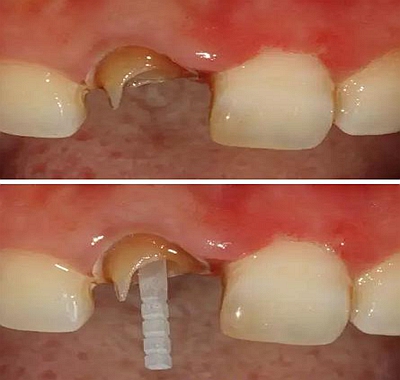

在操作的過(guò)程中要注意無(wú)菌操作,保證纖維樁的無(wú)菌狀態(tài)。推薦將樹(shù)脂核堆好之后再截?cái)嗬w維樁,而不是截?cái)嗪笤僬辰印H缦聢D:

10、排齦精修